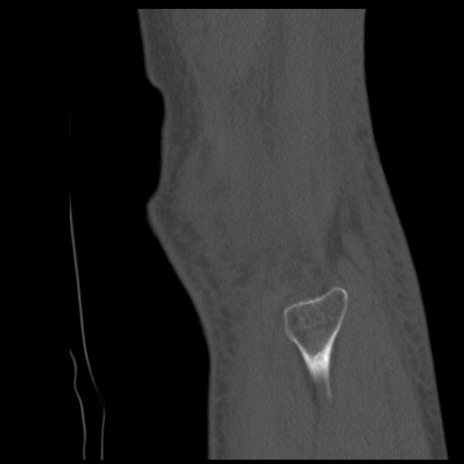

症例28 右膝関節CT(矢状断像)

右膝関節CT